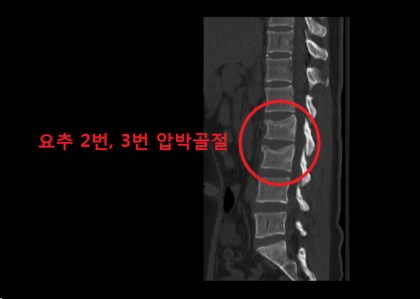

이 사건의 의뢰인은 상대방이 동석한 교통사고 피해자로서 사고 후 요통으로 ○○병원 응급실에 내원하였고 “제2요추폐쇄증후군” 진단을 받았다. 방사선 검사에서 “압박 골절”이 나타났습니다. 부상 초기에 척추의 추가 기형이 진행되거나 신경학적 증상이 나타나면 수술을 준비하고 며칠 동안 경과를 지켜보십시오. 다행스럽게도 통증은 신경학적 증상 없이 차차 가라앉았고, 정형외과를 통한 보존적 치료만이 상당 기간 지속되다가 치료가 종료되었다.

진단